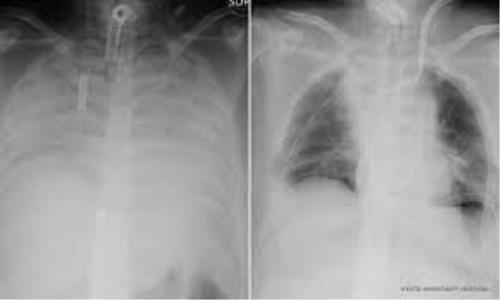

پیوند ریه از یك اهدا كننده زنده به بیمار مبتلا به كووید-19